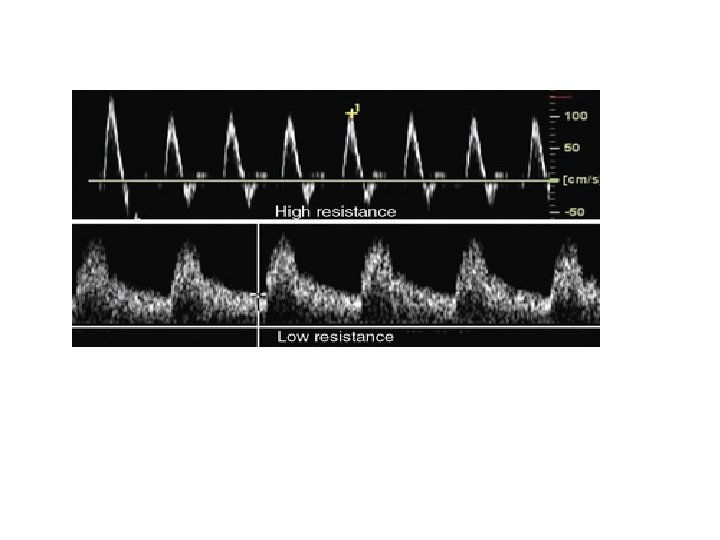

Peripheral Resistance Low resistance flow: Flow of a continuous (steady) nature feeding a dilated vascular bed. lots of flow in Diastole Going to organs

High resistance flow: Flow of a pulsatile nature. Between incident pulses, hydraulic reflections travel back up the vessel from the periphery producing flow reversals in the vascular compartment. Example arteries: ECA, subclavian, aorta, iliac, extremity arteries, fasting SMA

The reversal component of a high resistant signal may disappear distal to a stenosis because of decreased peripheral resistance, secondary to ischemia. Doppler flow distal to a significant stenosis is lower resistance. In addition, it is more rounded in appearance and is weaker in strength.

A normally high resistant (biphasic or triphasic) signal may become monophasic as it approaches the significant stenosis and or arterial obstruction. Doppler flow proximal to a significant stenosis is higher resistant in quality (could have no diastole or minimal diastole).